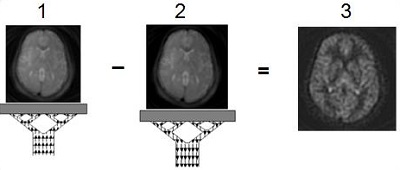

Two sets of images are acquired: one with the spatially selective inversion pulse (inverted blood) and one without the spatially selective inversion pulse (non-inverted blood). These two data sets are subtracted, which removes signal from the static background and the result is images that are proportional to cerebral blood flow. Multiple data sets are acquired to make a CBF image.

Figure 4. CBF image

Table 3. Image legend

NumberDescription

1Inverted blood, control image

2Non-inverted blood, label image

3CBF image